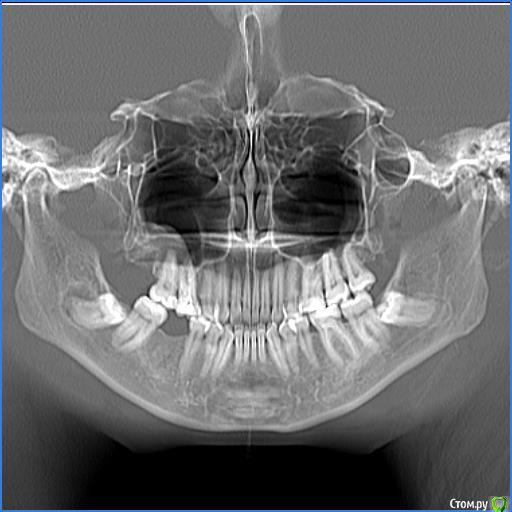

Юлия2386 Опубликовано 30 июля, 2020 Поделиться Опубликовано 30 июля, 2020 Добрый день, уважаемые врачи! Прошу вашей помощи, так как уже замучалась я конкретно. У меня уже 9 месяцев боли в правой стороне лица давящего характера. Давит на лоб, глаз, иногда висок. С декабря 2019 выявили фронтит-гайморит, проходила лечение у Лора и ещё невролога. Окончательного результата по выздоровлению за это время не достигнуто. Видимо это одномерный гайморит, так как постоянно какое-то воспаление формировалось у зубов 1.6;1.7;1.8. Многие стоматологи не видят проблем в зубе 1.6. Посоветовали удалить зуб 1.8 так как там был глубокий десневого карман. Удалила, а воспаление разрослось ещё больше (после удаления поцарапала щеку зубом 1.7, возможно из-за этого разрослось воспаление?!) После удаления прошёл месяц, а картина сейчас такая https://yadi.sk/d/ziceEN_jVZ9IkwВ итоге последний врач сказал, что все-таки проблема идёт от зуба 1.6, так как не запломбирован один канал, но из-за того что у зуба входят корни в гайморовых пазуху, лечить его не видет смысла, порекомендовал его удалить и через лунку вычиститься всю слизь, но он этим не занимается. Теперь я замешательстве и не знаю, что мне с этим делать, а самое ужасное, что глаз от этого болит( Уважаемые доктора, очень прошу вашей помощи, выскажите пожалуйста ваше мнение и может посоветуете к кому с этим можно обратиться в Москве. Ссылка на комментарий

wladdX Опубликовано 31 июля, 2020 Поделиться Опубликовано 31 июля, 2020 Представленная спиральная КТ не позволяет детально рассмотреть корневые каналы зубов и тп, чтобы получить какое-то внятное суждение.На уровне зубов 18, 17 и 16 есть локальное утолщение слизистой оболочки синуса и это всё, что из этого исследования можно выяснить. Адекватность обтурации корневых каналов зуба 16 оценить не представляется возможным (по крайней мере в моём понимании).Я бы порекомендовал сделать КЛКТ (конусно-лучевую компьютерную томографию), используемую в стоматологии. Ссылка на комментарий